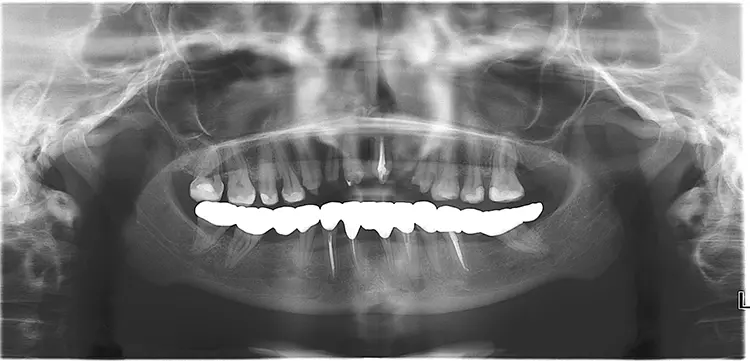

Als nächster Schritt wurde eine schablonengeführte Implantation für die definitive Versorgung im Unterkiefer gewählt (Nobel GuideTM, Nobel Biocare) (Abb. 9). Die Versorgung erfolgte mit verschraubten Einzelkronen (Lithiumdisilikat IPS e.max Press, Ivoclar) auf Titanabutments Universal Base Abutments (Nobel Biocare) und Multilink Hybrid-Abutment (Ivoclar) (Abb. 10).

Die Implantation (zweizeitiges Vorgehen) fand an den Positionen 036, 045 und 031 statt (Replace Select Tapered RP jeweils 8 mm und Nobel Active 3.0 im UK-Frontzahnbereich Länge 10 mm, Nobel Biocare) [21]. Zeitgleich wurde nach Implantatverschluss mit Deckschrauben eine ortständige Augmentation mit Knochenersatzmaterial (DBBM, Bio Oss®, Geistlich) durchgeführt, mit Kollagenmembran (BioGide®, Geistlich) stabilisiert und anschließend mit 5.0er Naht verschlossen.